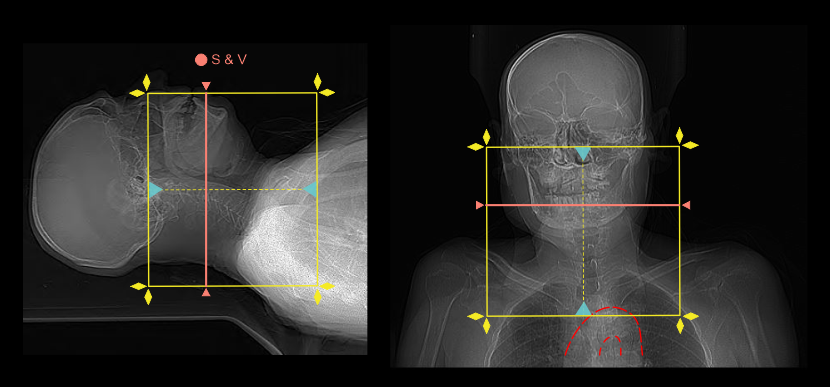

Triggering or bolus tracking method can be used to initiate the arterial phase because arterial enhancement can be viewed in real-time from the scan and view (S & V) slice, avoiding early or delay acquisitions. Manual start without ROI is recommended because it is challenging to recognize carotid arteries in pre-contrast S & V slice.

- Place the S & V slice at the mid part of the neck.

- Set S & V initiation time to 5 seconds from the contrast injection.

- Plan the scan direction for arterial phase from head to foot.